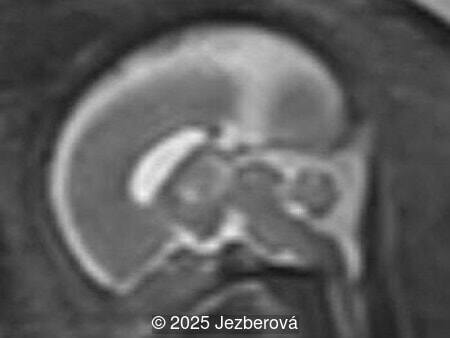

At 20 weeks, detailed ultrasound under conditions of severe oligohydramnios demonstrated absence of the typical box-shaped anechoic structure of the cavum septum pellucidum (CSP). The frontal horns of the lateral ventricles appeared narrow and pointed, giving the characteristic “bull’s horns sign.” Multiplanar and 3D reconstructions confirmed the presence of the corpus callosum, while the CSP was absent. Other midline and posterior fossa structures appeared normal. The optic chiasm was partially visualized, although assessment was limited by technical conditions. Fetal magnetic resonance imaging (MRI) was subsequently performed and confirmed isolated agenesis of the CSP with preserved corpus callosum and posterior fossa structures. The optic chiasm and pituitary stalk are visible in the sellar region, but the pituitary gland itself is not clearly identified in the sella turcica as it is a very small structure. No additional central nervous system anomalies were detected.